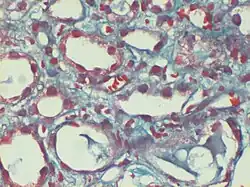

Trichrome de Gomori

Le trichrome de Gömöri est une coloration histologique utilisée sur le tissu musculaire[1],[2]. Elle peut être utilisée pour dépister certaines formes de myopathie mitochondriale.